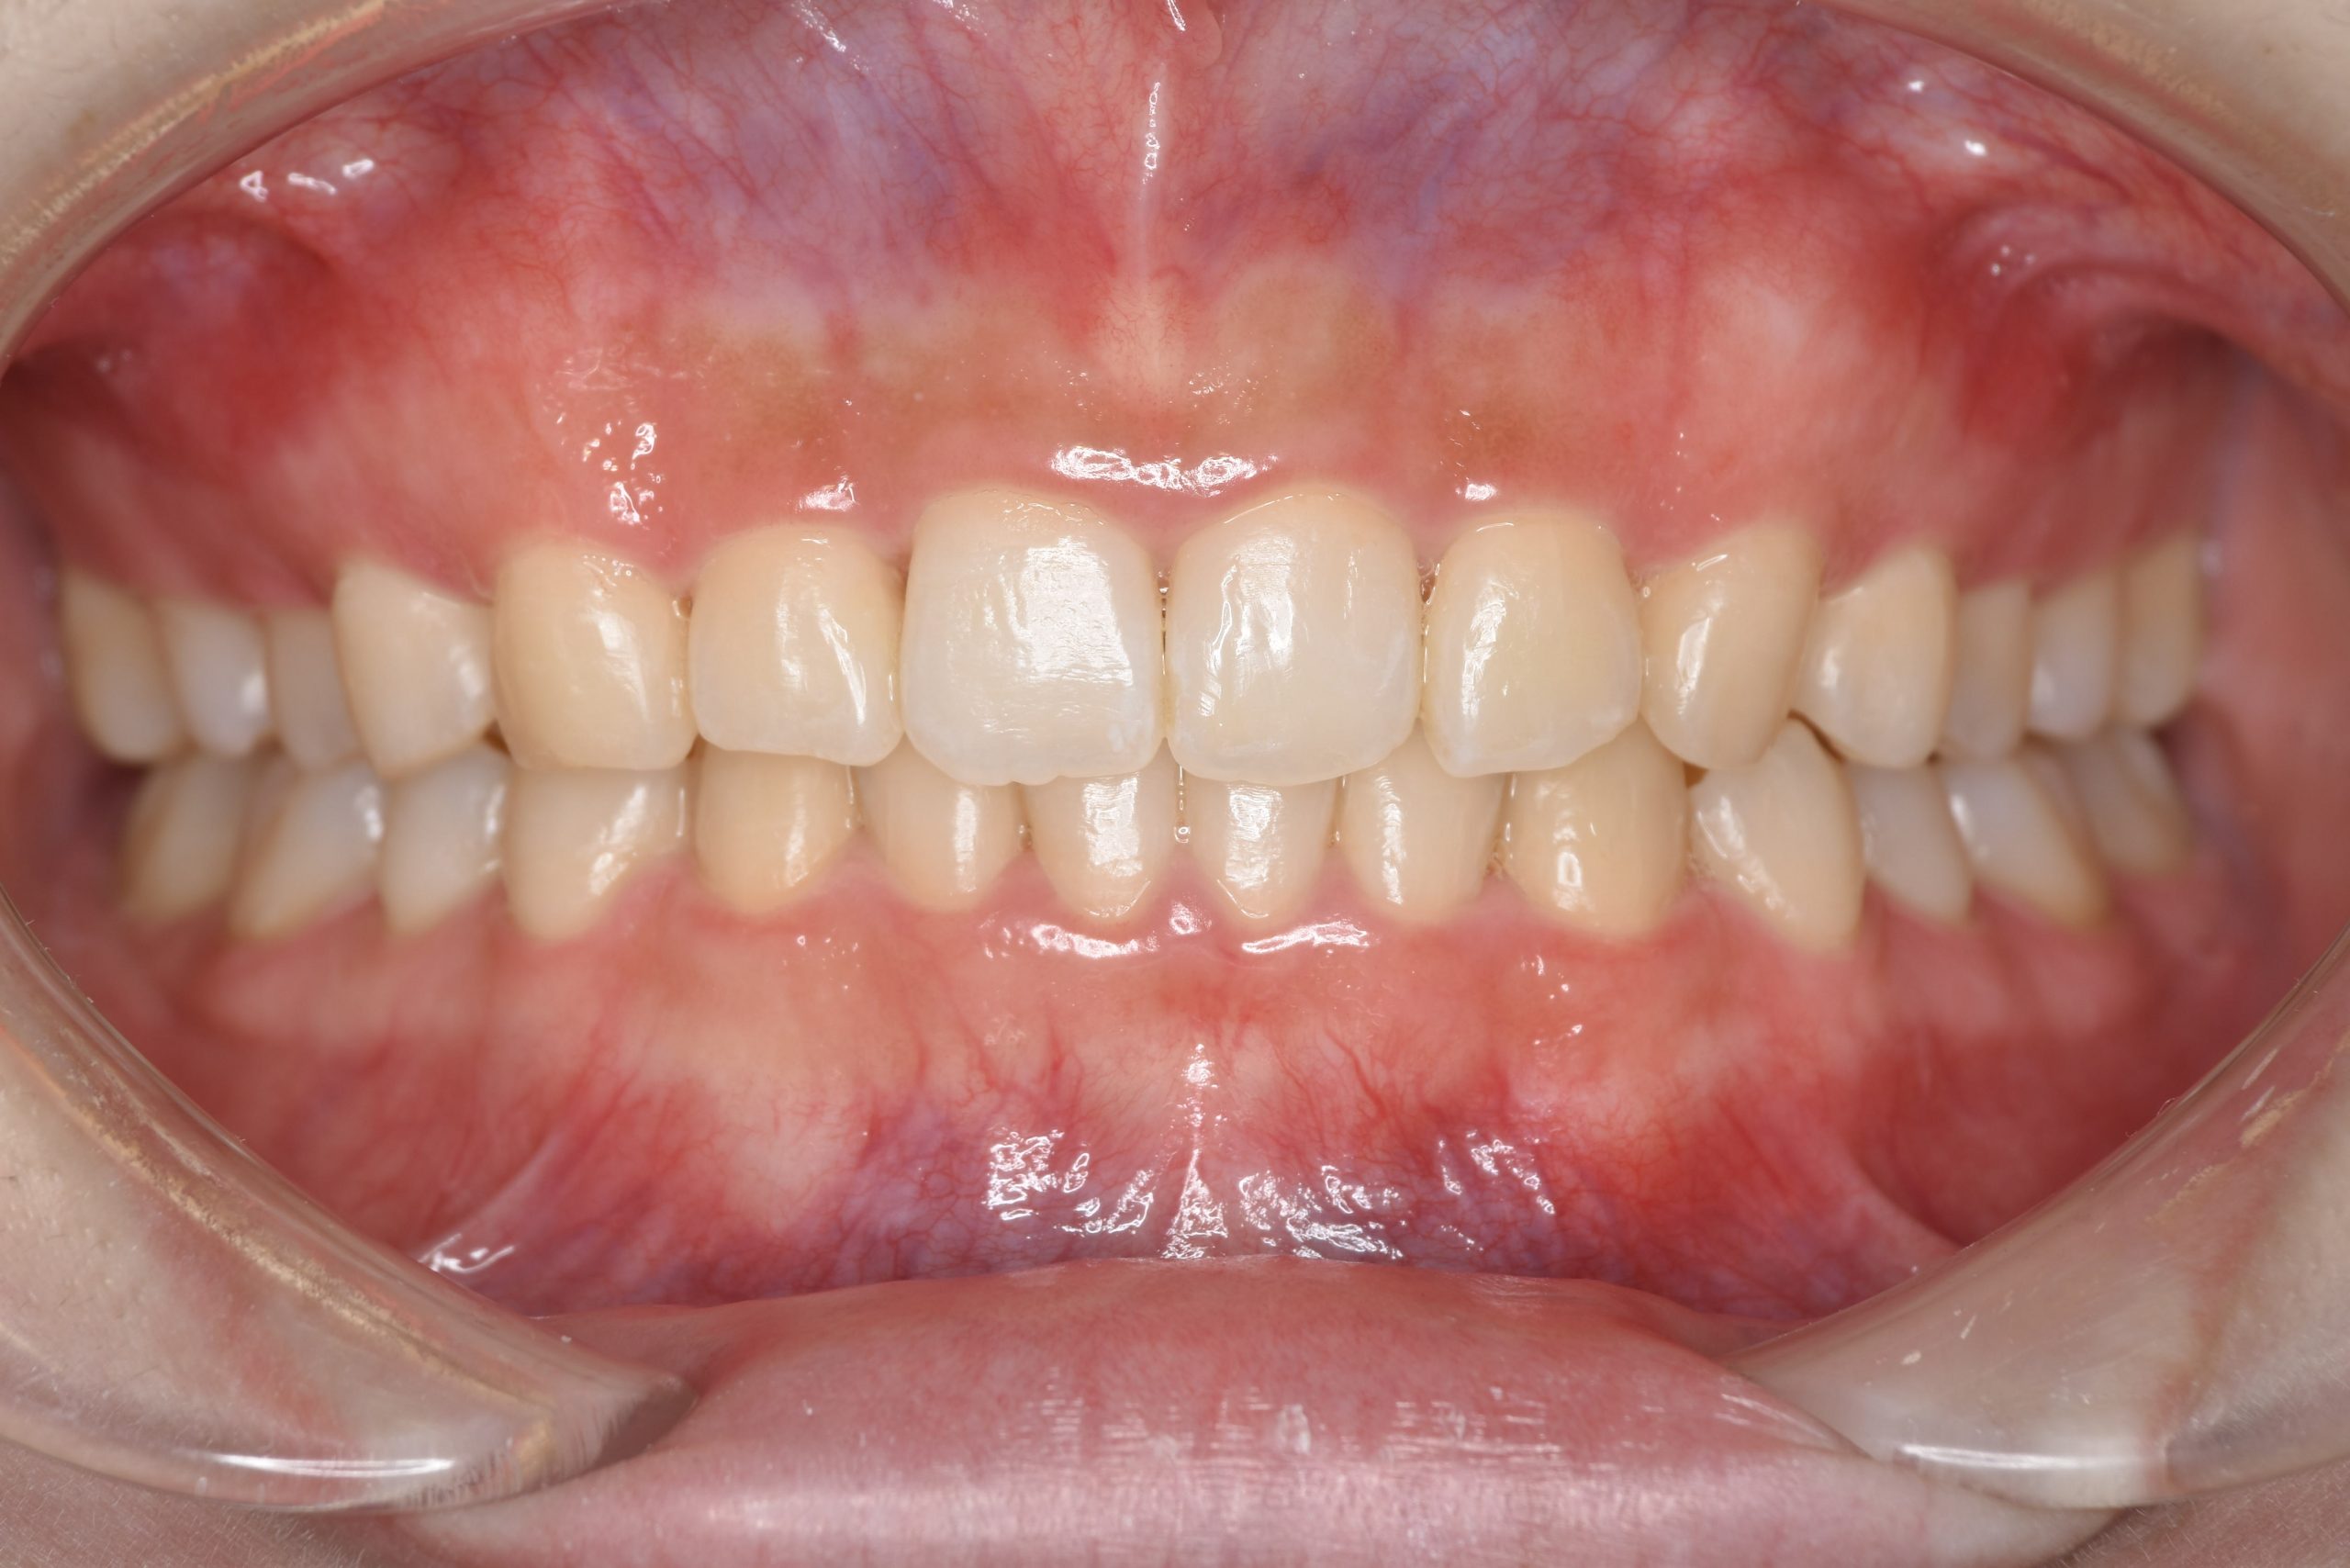

アフター

インビザライン矯正治療|症例_315